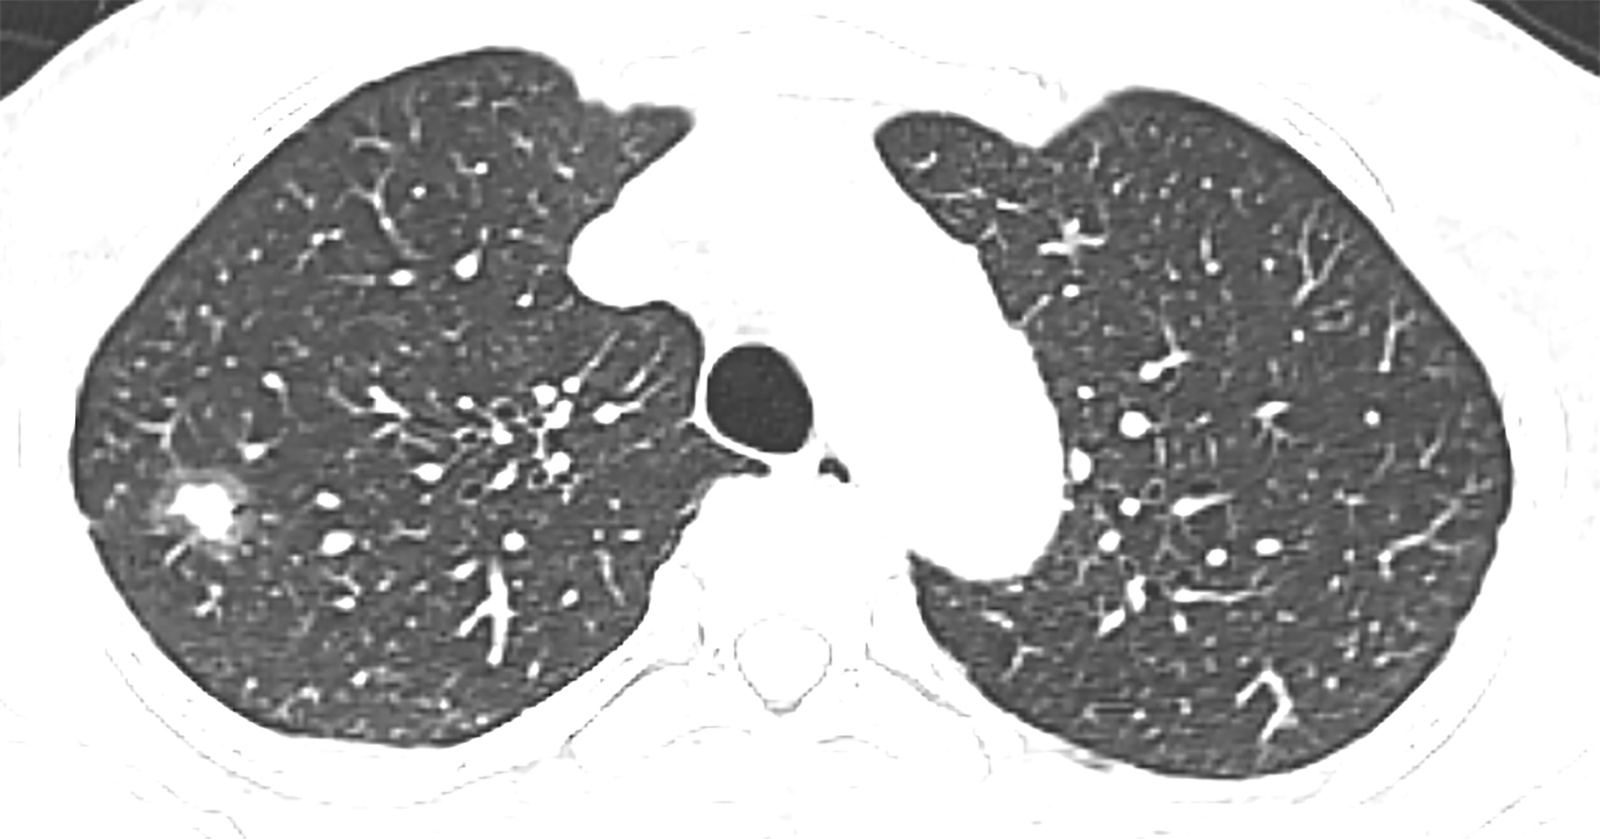

单因素分析显示,CEA、肿瘤最大径、实性成分最大径、CTR、cT分期、边界、分叶征、毛刺征与STAS表达状态显著相关(P均<0.05),将上述特征纳入多因素logistic回归分析,结果表明CEA、肿瘤最大径、cT分期以及毛刺征是STAS阳性的独立预测因素(P均>0.05) (表2)。图1展示了1例STAS阳性患者的CT图像。

(a) (b) (c)

Figure 1. A 57-year-old male patient with STAS-positive lung adenocarcinoma. Axial (a), coronal (b), and sagittal (c) CT images show a part-solid nodule in the right upper lobe, with a well-defined boundary,containing a solid component and peripheral lobulation

1. STAS阳性肺腺癌患者,男,57岁。横轴位(a)、冠状位(b)、及矢状位(c) CT图像示右肺上叶部分实性结节,边界清晰,内可见实性成分,周边可见分叶征